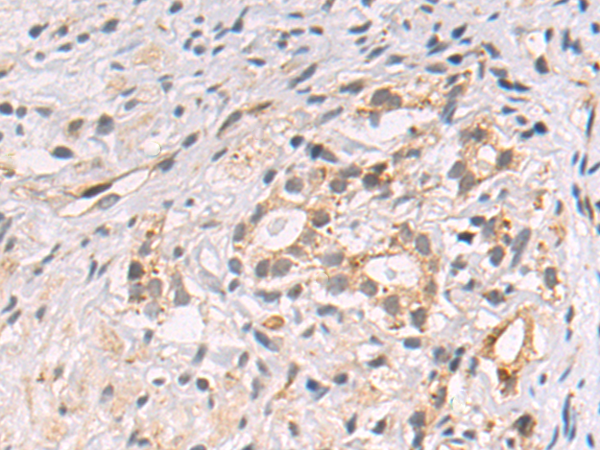

分类: 科研抗体货号: P10646别名: C10orf22应用: WB,IHC反应种属: Human, Mouse